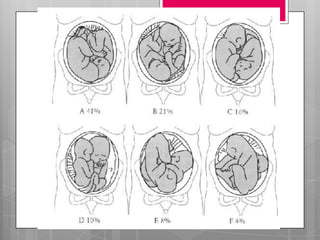

 La elección de la vía del parto va

Determinado por la EG, peso estimado y

la la presentación de los gemelos.

 40% en presentación Cefálica al

momento de las contracciones.

 Si el segundo viene =, prosigue el parto, si

cambia se usan 2 maniobras:

 > 32 SDG o peso >1500g, permitirá parto

vaginal siempre que el 1er gemelo este

presentación cefálica:

 1 cefálica- 2 cefálica: tipo mas fx, parto vaginal

 1 cefálica- 2 podálica: a la expulsión del 1ro, se

intentara el parto del segundo (elección)

 1 cefálica- 2 transversa: parto vaginal. El

segundo gemelo puede rotar

espontáneamente a longitudinal, si no, se hace

versión interna y gran extracción del 2 gemelo.

O cesárea

 1 podálica o transversa: cesárea,

independientemente de la estática del 2

gemelo

TRATAMIENTO DURANTE EL PARTO La elección de la vía del parto va Determinado por la EG, peso estimado y la la presentación de los gemelos.  Comprueba FC  40% en presentación Cefálica al momento de las contracciones.  Si el segundo viene =, prosigue el parto, si cambia se usan 2 maniobras:

 > 32SDG o peso >1500g, permitirá parto vaginal siempre que el 1er gemelo este presentación cefálica:  1 cefálica- 2 cefálica: tipo mas fx, parto vaginal  1 cefálica- 2 podálica: a la expulsión del 1ro, se intentara el parto del segundo (elección)  1 cefálica- 2 transversa: parto vaginal. El segundo gemelo puede rotar espontáneamente a longitudinal, si no, se hace versión interna y gran extracción del 2 gemelo. O cesárea  1 podálica o transversa: cesárea, independientemente de la estática del 2 gemelo